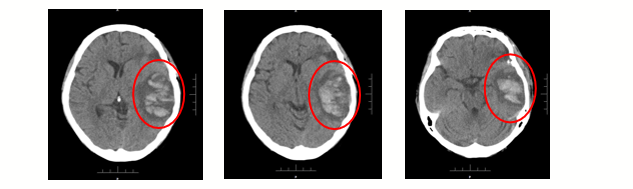

2021年6月,患者接受全脑放疗6次后,出现突发头痛、头晕、嗜睡及失语,急诊脑部CT显示颅内出血,开颅探查,行左颞叶血肿清除术,术后病理未见转移性癌细胞。6月20日起停用吡咯替尼+卡培他滨。

图4 急诊脑部CT示颅内出血